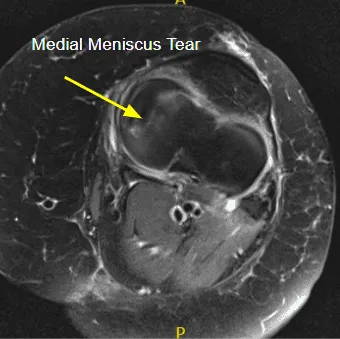

MRI of the left knee suggested radial tear of the medial meniscus and medial collateral ligament sprain/tear.

A lateral anterior entry portal was made and the arthroscopy was inserted. A medial anterior portal was made using a spinal needle. Examination of the medial tibial compartment showed a radius tear of the posterior body of the posterior horn of the medial meniscus. Resection of the margins of the tear was performed with the use of biters and shavers which achieved balanced margins.

There was also a horizontal tear which was debrided. Balanced margins would be achieved. There was Grade III to Grave IV osteoarthritis of the medial femoral condyle. Examination of the infrapatellar notch showed an intact ACL.